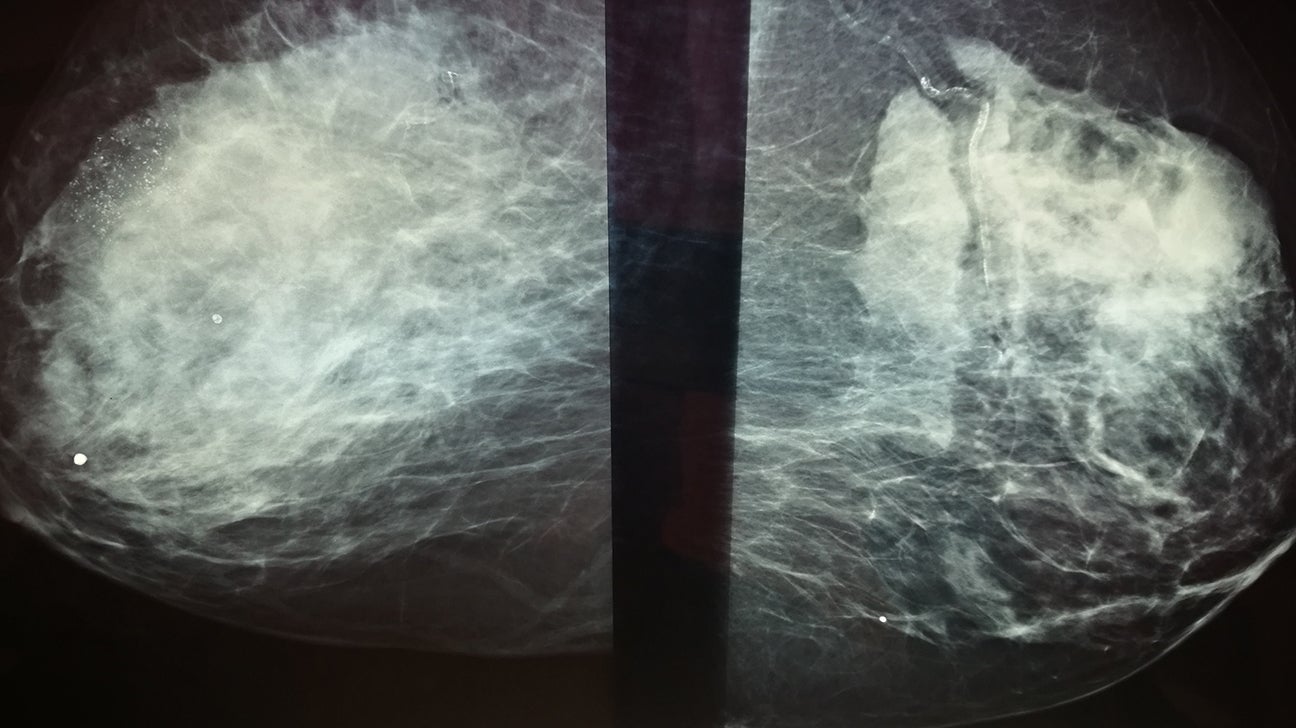

There’s a change from the last mammogram.

They appear as white spots or flecks on a mammogram but can't be felt during a breast exam. A new group has formed. For women treated for breast cancer in the past, calcifications may also be due.